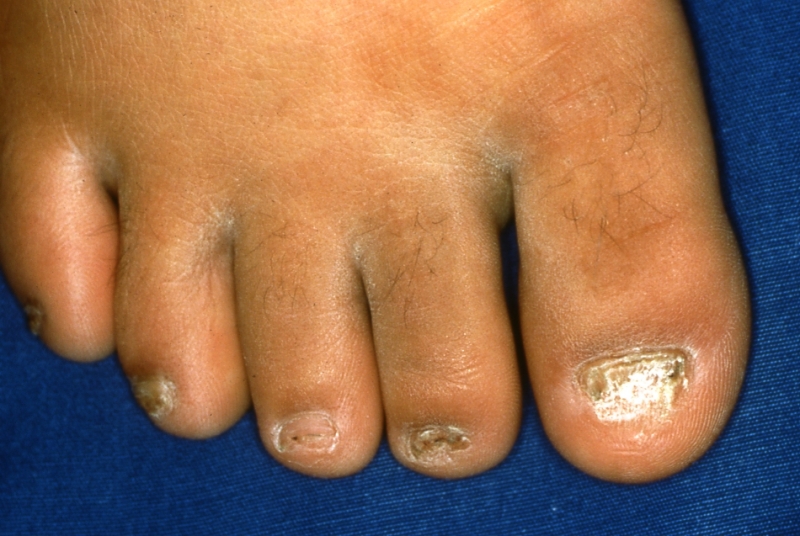

1.爪白癬

爪白癬の治療の第一選択は飲み薬です。塗り薬ではなかなか治りません。

爪の水虫(爪白癬)や、カチカチタイプの水虫(角質増殖型足白癬、一見“ひび割れ”、“あかぎれ”と思わせる病型)などに代表される治りにくい水虫の、治療の選択は飲み薬が一番なのです。